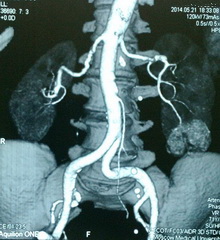

Рис. №2. Мультиспиральная компьютерная томография органов мочевой системы с контрастированием. Опухоль нижнего сегмента левой почки до 5 см, активно накапливающая контрастное вещество.

Из анамнеза: по месту жительства при УЗИ органов мочеполовой системы заподозрено образование левой почки. Консультирована в клинике урологии Первого МГМУ им. И.М. Сеченова, при УЗИ и МСКТ органов брюшной полости наличие образования в нижнем сегменте левой почки подтверждено. Госпитализирована в онко-урологическое отделение в плановом порядке для выполнения оперативного пособия.